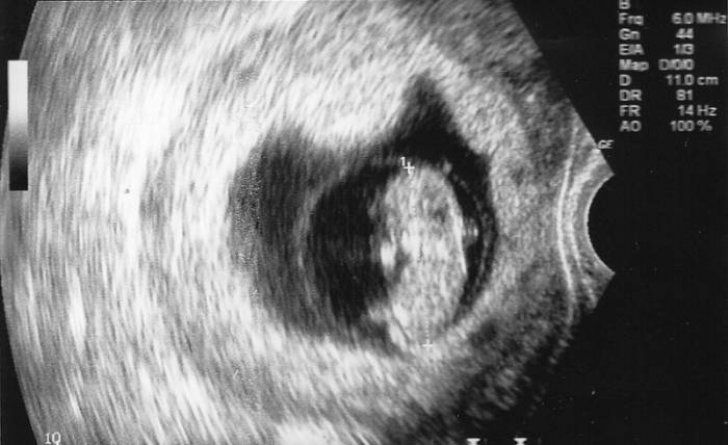

25 nov. 2016, 20:07MondenDoctorul a văzut ecografia și i-a spus să avorteze. A refuzat. După 7 luni a născut: Dumnezeule!

4 oct. 2016, 12:53ActualDoctorul a văzut ecografia și i-a spus să avorteze. A refuzat. După 7 luni a născut: Dumnezeule!